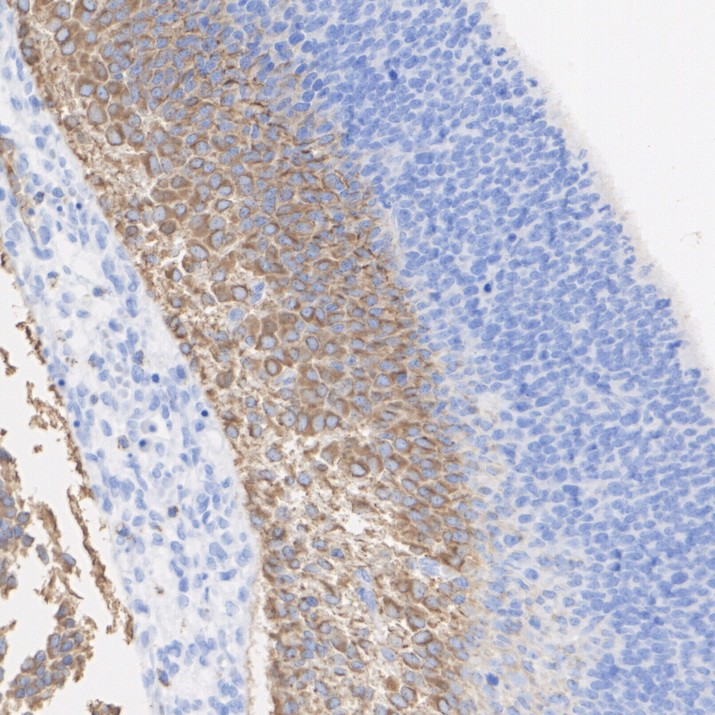

Immunohistochemical analysis of paraffin-embedded human cerebellum tissue with Rabbit anti-Beta III Tubulin antibody (HA751554) at 1/4,000 dilution.

The section was pre-treated using heat mediated antigen retrieval with Tris-EDTA buffer (pH 9.0) for 20 minutes. The tissues were blocked in 1% BSA for 20 minutes at room temperature, washed with ddH2O and PBS, and then probed with the primary antibody (HA751554) at 1/4,000 dilution for 1 hour at room temperature. The detection was performed using an HRP conjugated compact polymer system. DAB was used as the chromogen. Tissues were counterstained with hematoxylin and mounted with DPX. -